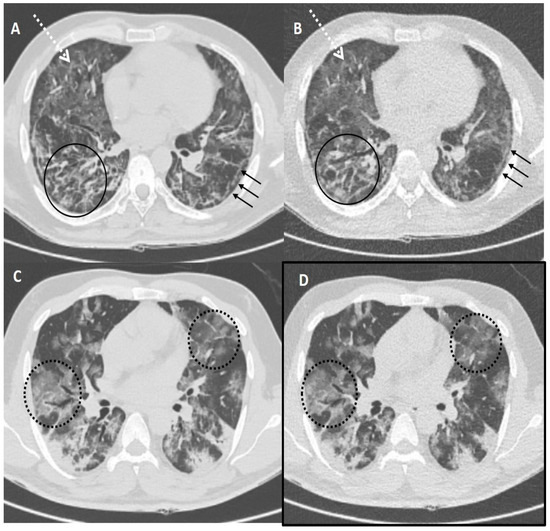

Figure 4.

Comparison of standard-dose CT (SDCT) chest and ultra-low dose CT (ULDCT) chest in two different COVID-19 patients: (A,B) A 51-years old male with SDCT (A) and corresponding ULDCT (B) images showing interlobular septal thickening/reticulation (black circles) and parenchymal bands (black arrows), with interspersed areas of GGOs in both lungs (dotted white arrows). (C,D) A 45-years old male patient with SDCT chest (C) and corresponding ULDCT chest (D) showing areas of GGOs with interlobular septal thickening giving a crazy-paving pattern (dotted circles). The CT severity score calculated on SDCT and ULDCT was found to be similar in both patients, while the effective radiation dose for SDCT was 4.63 mSv and 4.81 mSv, and for ULDCT was 0.26 mSv and 0.28 mSv, respectively.